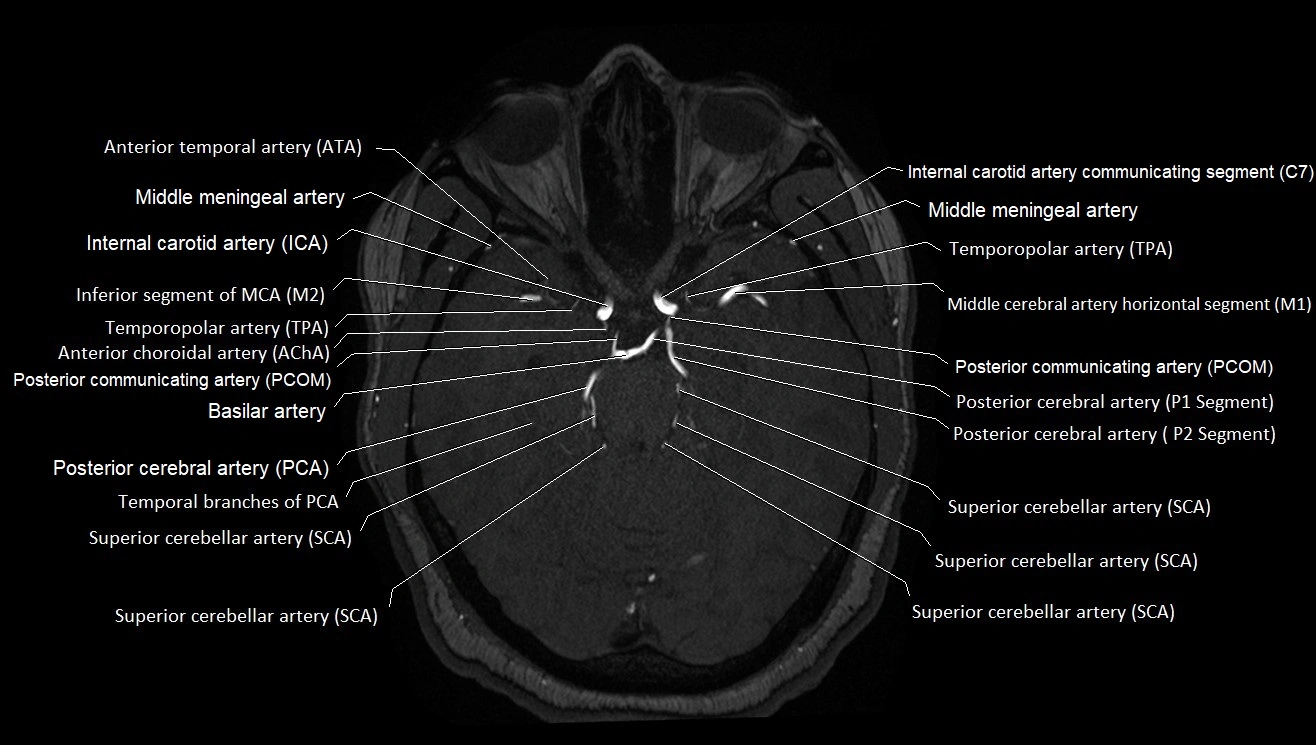

MRI images

image